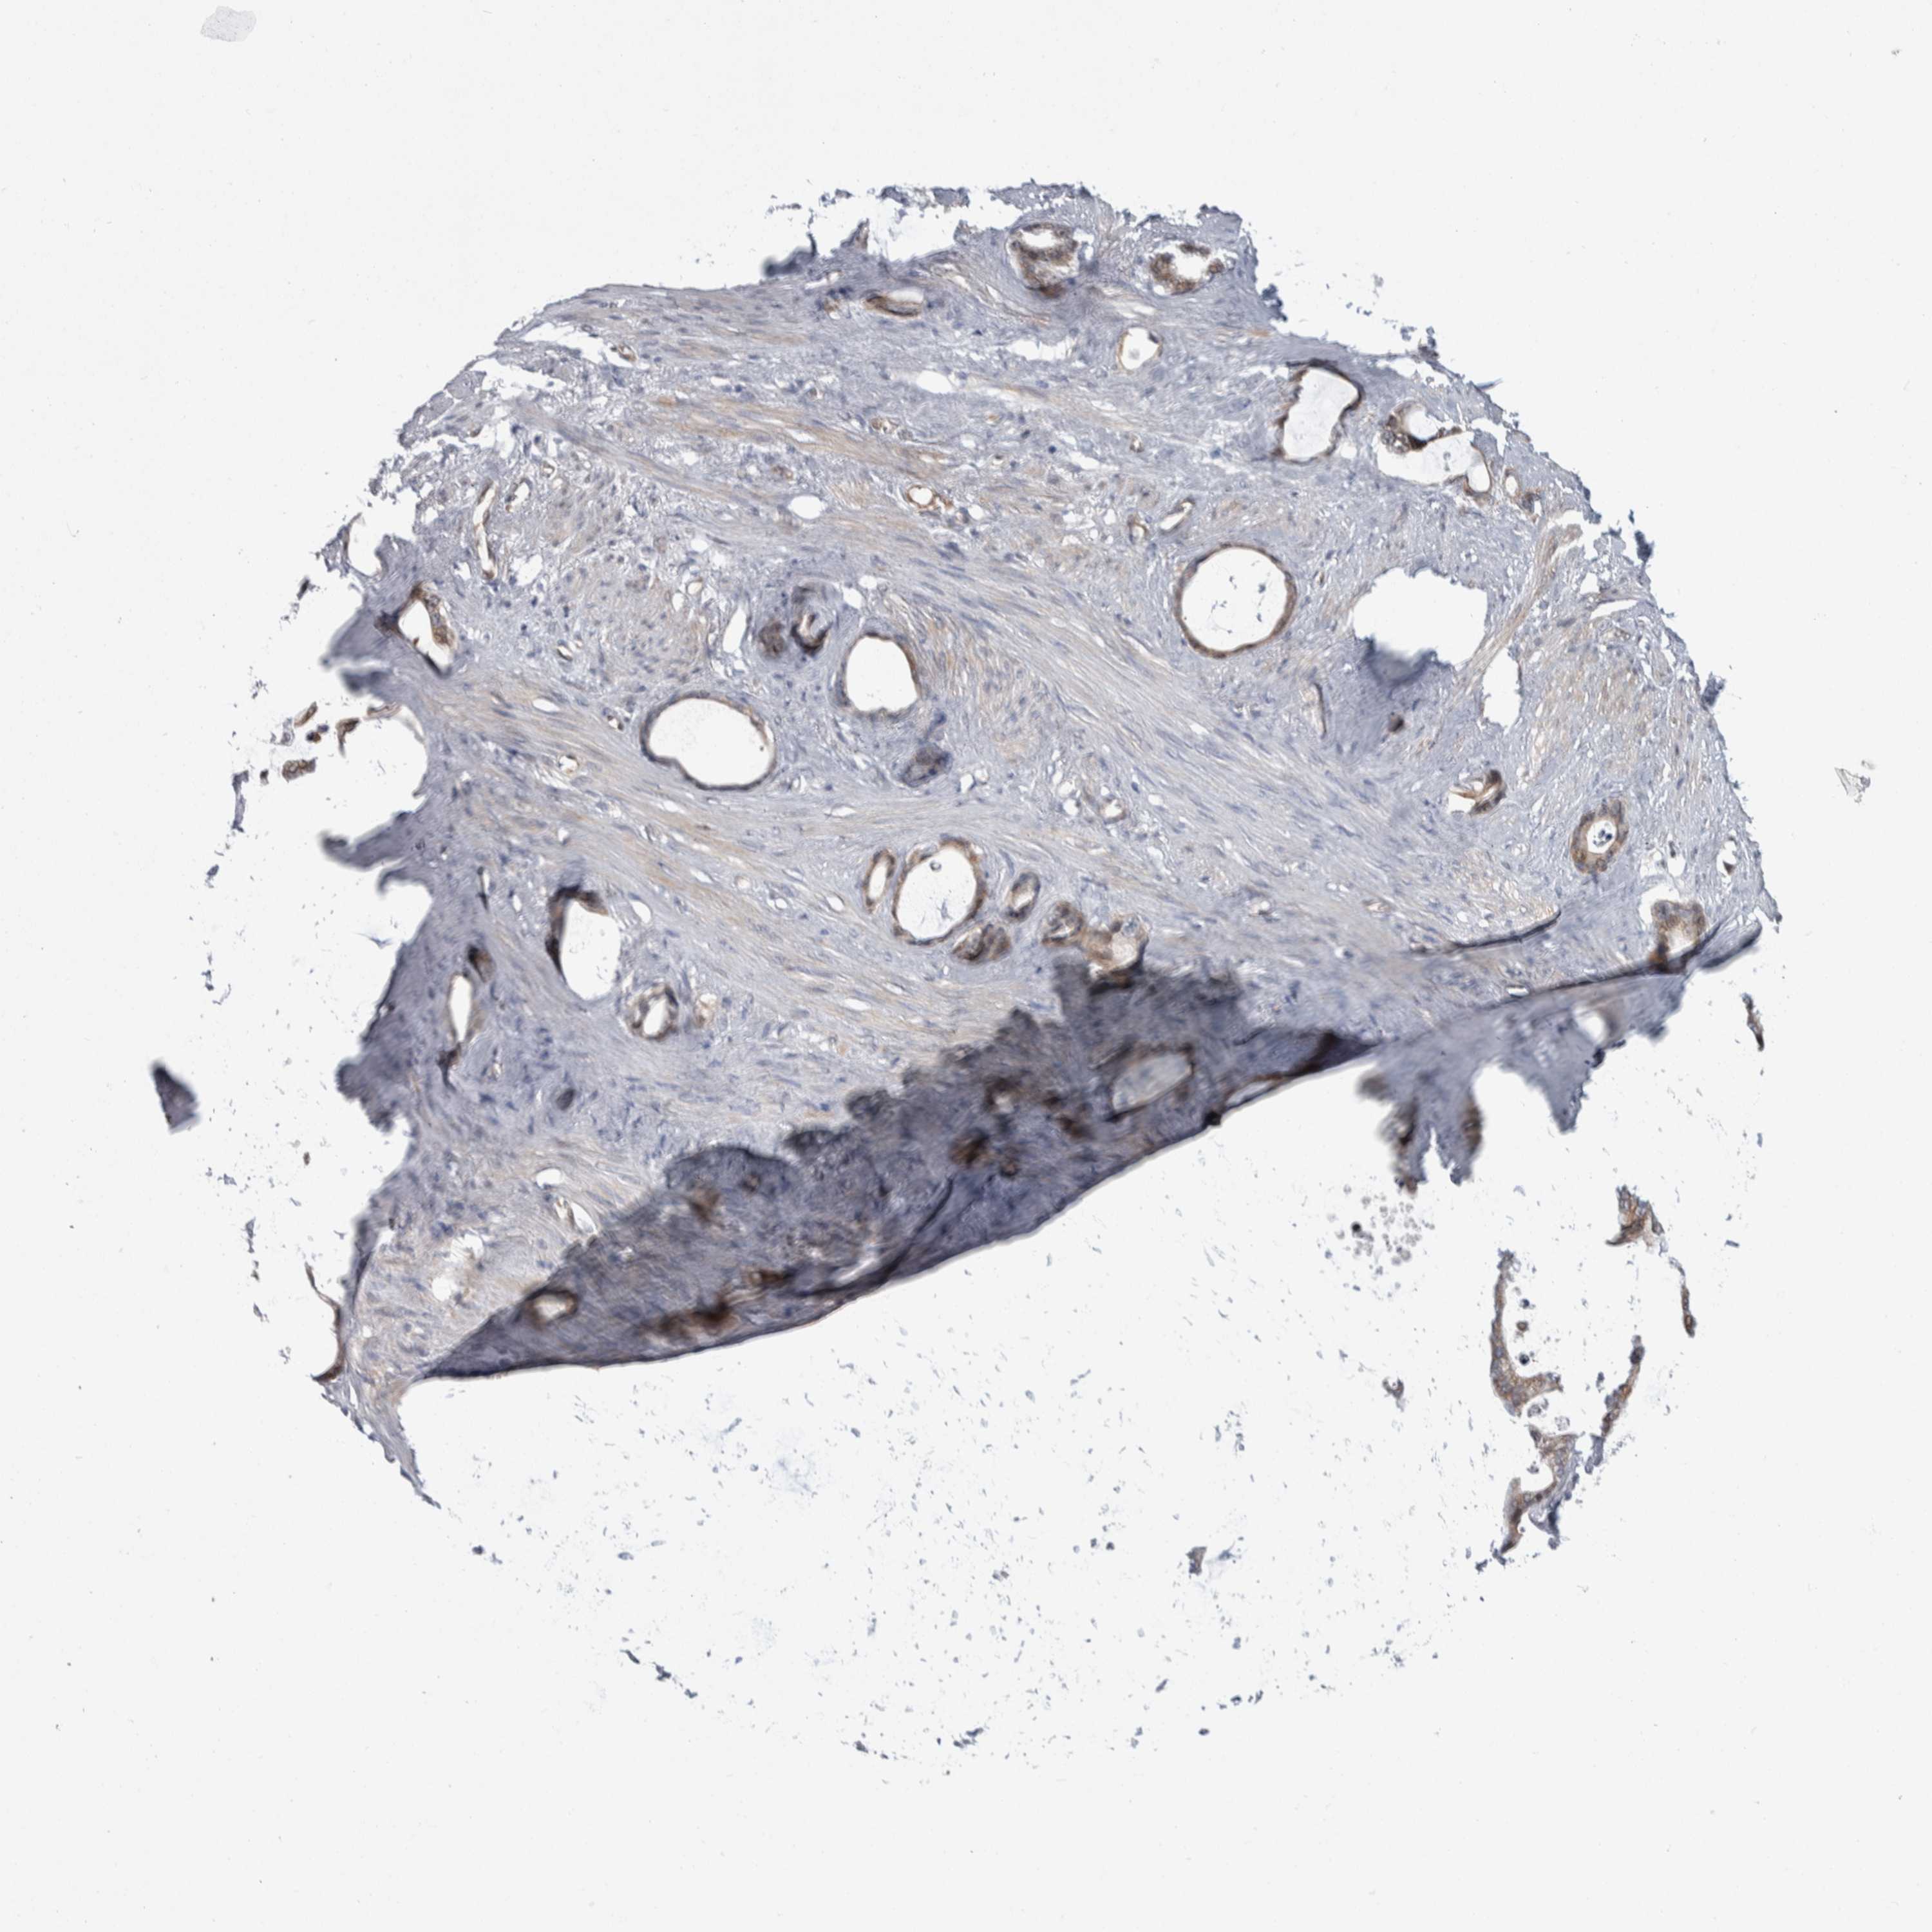

STOMACH CANCER - Protein expressioni

A mouse-over function shows sample information and annotation data. Click on an image to view it in a full screen mode. Samples can be filtered based on level of antibody staining by selecting one or several of the following categories: high, medium, low and not detected. The assay and annotation is described here.

Note that samples used for immunohistochemistry by the Human Protein Atlas do not correspond to samples in the TCGA dataset.

Antibody stainingi

Antibody staining in the annotated cell types in the current human tissue is reported as not detected, low, medium, or high, based on conventional immunohistochemistry profiling in selected tissues. This score is based on the combination of the staining intensity and fraction of stained cells.

Each image is clickable and will lead to virtual microscopy that enables deeper exploration of all samples and also displays staining intensity scores, fraction scores and subcellular localization as well as patient and tissue information for each sample.

HPA005695

CAB022068

CAB035999

CAB080052

CAB080054

CAB080098

Staining

High

Medium

Low

Not detected

Intensity

Strong

Moderate

Weak

Negative

Quantity

>75%

75%-25%

<25%

None

Location

Nuclear

Cytoplasmic/membranous

Cytoplasmic/membranous,nuclear

Adenocarcinoma, NOS

Adenocarcinoma, High grade